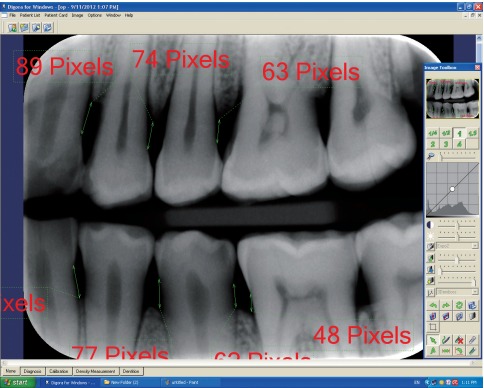

رادیوگرافی بایت وینگ

Evaluation of alveolar crest bone loss via premolar bitewing radiographs : presentation of new method

Evaluation of alveolar crest bone loss-2014